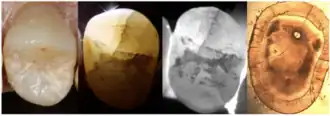

Enamel Fracture

4. Transillumination

Transillumination involves using fiber-optic light to illuminate the tooth surface, with light diffraction at the crack helping to locate it (Chanchala HP et al., 2022).

Microscopic Detection

5. Microscope detection

Cracks with width less than 18 μm are difficult to detect with the naked eye, making dental microscopes an essential tool for crack identification.